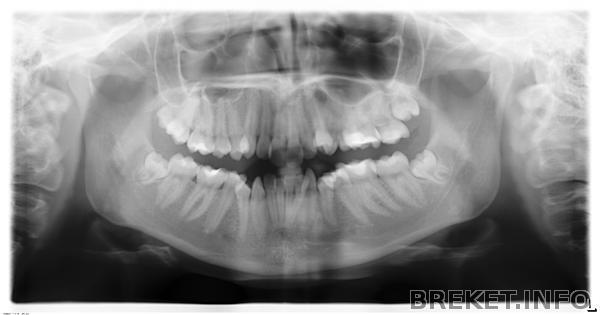

8-ки еще не прорезались, орт про них ничего не говорил, удалять будем 5-ки. Я боюсь, что в процессе лечения мне скажут удалять зубы мудрости =( а это, по-моему, самое ужасное, особенно непрорезавшиеся...

А еще меня смущает 8-ка на ВЧ справа, которая стоит бок о бок с дистопированной(!) 7-ой (на снимке все это дело слева и не совсем понятно, потому что друг на друга они залезают)...что-то я за это волнуюсь